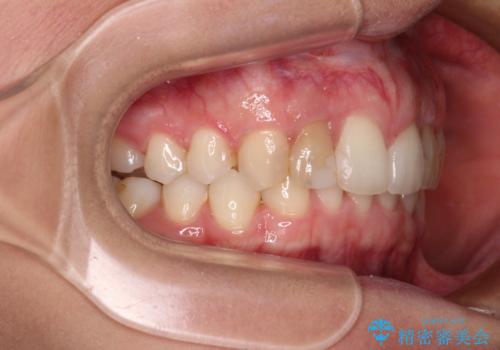

- 前歯の歯並びと神経を取って変色してしまった前歯を気にして来院された患者様です。

上下前歯の歯列不正はインビザラインにより整え、その後に、前歯2本をオールセラミッククラウンにて補綴治療することとしました。

下顎前歯が1本欠損しており、下顎歯列の大きさが本来よりも小さいため、上顎歯列とのバランスが悪く、深い咬み合わせになっていました。

上顎にIPRを多用して歯列の大きさを小さくするよう試みましたが、理想的な咬み合わせまでには改善させることはできませんでした。